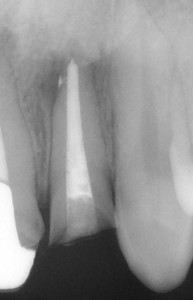

この歯の場合には、根の先近くで神経のあった空間(根管)が枝分かれしていました。

レントゲンではその中にまで緊密に充填できていることがわかります。

このような治療を行なうことができれば、その歯にかぶせるセラミックスも長持ちすることにつながります。

(例えばですが、この細い枝分かれまでケアできなかった場合、歯に違和感が長く残り歯根端切除という手術が必要となったり、最悪抜歯となってしまう可能性もなくはありません。)